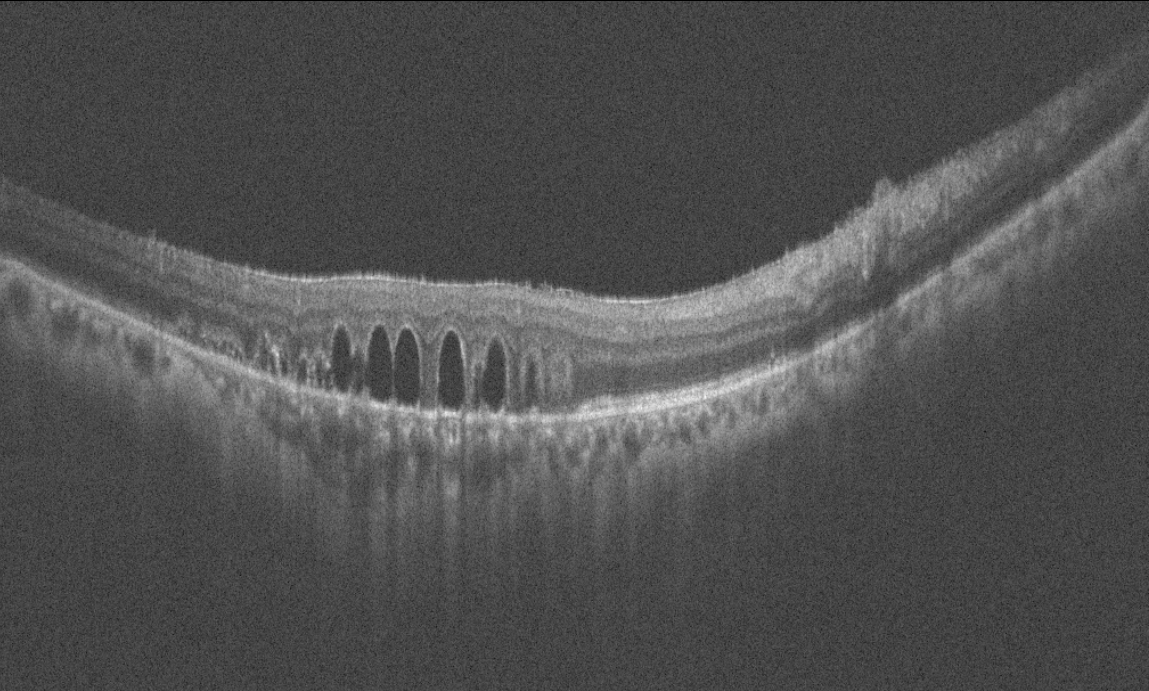

Sağ gözde görme keskinliği 0,3 düzeyinde olan 60 yaşındaki erkek hasta görme azlığı şikayeti ve retina bulguları nedeniyle kliniğimize refere edilmiştir. Hastanın başka bir klinikte 1 yıl önce retina cerrahisi geçirme öyküsü mevcuttur. Hastanın sağ göz renkli fundus, floresein anjiyografi ve optik koherens tomografi görüntülerini görmektesiniz. Bu bulgulara göre tanınız ve resimde fark edilen bulgu nedir? Lütfen cevabınızı aşağıya yazınız.

Bu ay size sağ gözünde görme keskinliği 0,3 düzeyinde olan, 1 yıl önce geçirilmiş retina cerrahisi öyküsü bulunan, 60 yaşındaki erkek hastanın renkli fundus, floresein anjiyografi ve optik koherens tomografi görüntüleri eşliğinde tanısını ve retina bulgusunu sormuştuk.

Tanı: Retina dekolman cerrahisi sonrası retina altında kalmış olan sıvı perflorokarbon (dekalin-Perflorodekalin) damlacıkları’dır.

PFK sıvıları intraoperatif kullanımda güvenilir olmasına karşın oküler toksisite ve küçük parçalara ayrılma nedeniyle uzun süre gözde bırakılmamalıdır. Kimyasal toksisite, birleşiminde hidrojen varlığı gibi saflığın az olduğu durumlarda ortaya çıkar. Bu durumda lipoproteinlerin absorbsiyonu artmakta, fibroblastik reaksiyon tetiklenerek preretinal membranlar gelişmektedir. Göz içerisinde uzun süre kaldığında retina sinir lifi katında vakuoller, dış pleksiform tabakada psödomyelin birikimi, fotoreseptörlerde kısalma gözlenir.

Retina alt katında hasar çok daha fazla olduğu için burada kimyasal toksisiteden çok mekanik hasar düşünülür. PFK sıvıları jet akımla verildiğinde retina altına gidebilir ve küçük parçacıklar halinde bir bölgede kalabilir. Fovea altına gittiğinde fotoreseptörlere toksiktir ve alınması gereklidir.